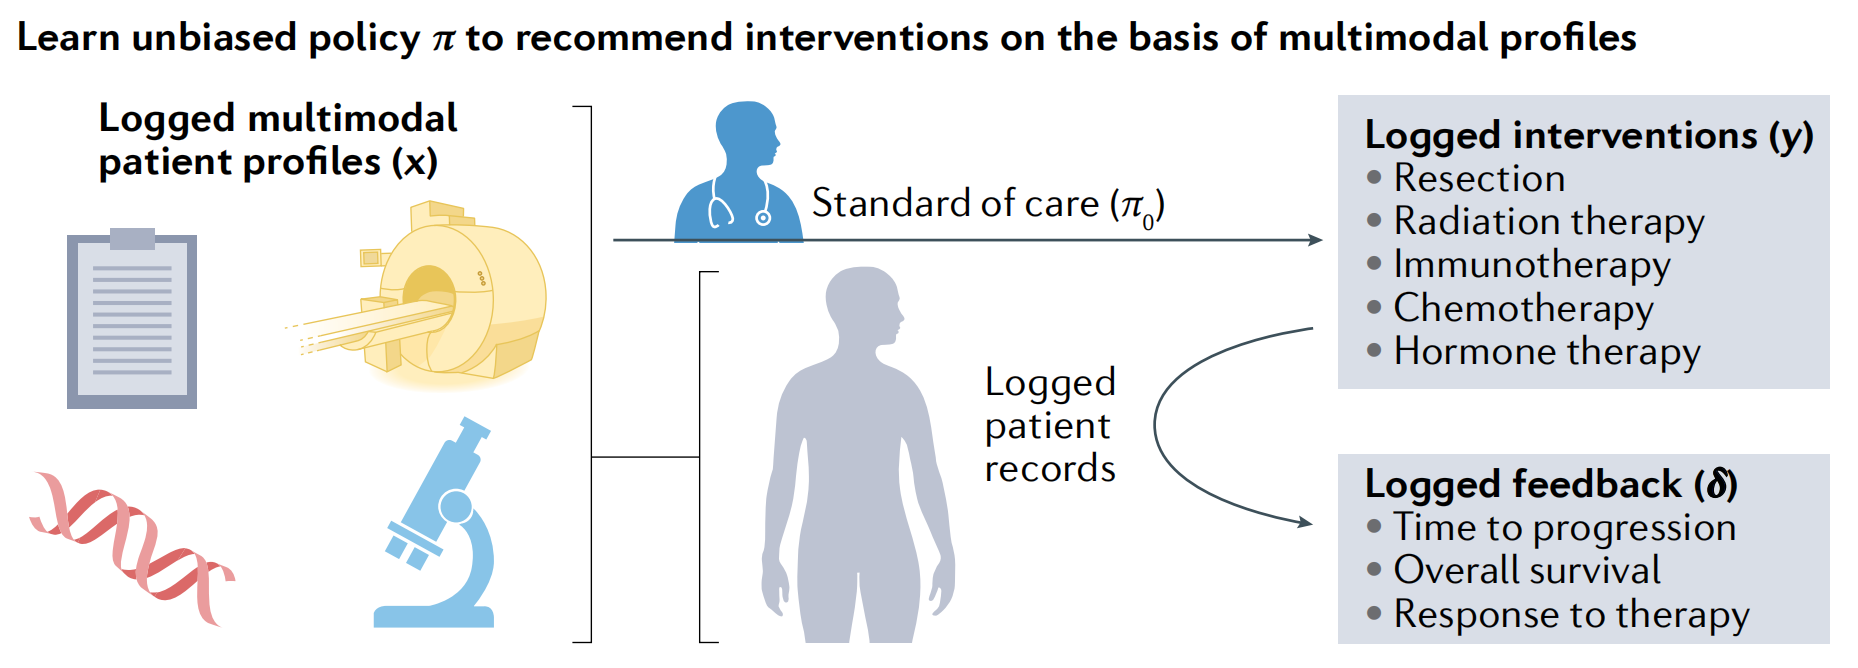

图 1 展示了用于整合的示例数据模态,包括放射学、组织病理学和基因组学信息。这个图表以视觉方式呈现了如何从不同数据源中提取特征,并将其用于构建一个综合的、多模态的数据集,以便于进行精准肿瘤学研究。

以下是对这些数据模态的解释:

-

放射学(Radiology):

- 放射学图像(如CT扫描、MRI、PET扫描)提供了关于肿瘤位置、大小和形态的视觉信息。

- 通过放射组学(radiomics)技术,可以从这些图像中自动提取定量特征,如肿瘤的密度、形状和纹理特征。

-

组织病理学(Histopathology):

- 组织病理学涉及对组织样本的细胞和组织结构进行显微镜检查。

- 通过数字化染色玻片(如H&E染色),可以进行图像分析,以识别肿瘤细胞的形态特征、组织结构和肿瘤-免疫系统界面。

-

基因组学(Genomics):

- 基因组学数据包括肿瘤组织的基因组测序结果,可以揭示遗传变异、突变负荷、拷贝数变异等信息。

- 这些数据有助于了解肿瘤的分子特征,预测对特定治疗的敏感性和耐药性。

通过深度学习或其他机器学习技术,可以从每种模态中提取特征,并将这些特征用于训练模型,以预测临床结果或发现新的生物标志物。

整合这些不同模态的数据对于精准肿瘤学至关重要,因为它允许医生和研究人员更全面地了解肿瘤的生物学特性,并为每个患者定制更有效的治疗策略。通过分析这些多模态数据,研究人员可以发现不同数据类型之间的关联,从而更好地预测治疗反应和疾病进展。

随着越来越多的数据集被注释和集成,肿瘤学将从多模态推荐系统中受益,类似于从单模态基因表达数据推断癌症药物反应[100]。回顾性观察研究中没有匹配的对照组,这会偏置训练数据,并需要反事实ML等方法来从记录的干预和结果中学习准确的推荐策略[101]。

图 5 描述了推荐系统如何利用回顾性数据来协助临床决策。在医疗领域,推荐系统可以基于历史的患者记录(例如,治疗前CT扫描和H&E染色的活检样本)和治疗结果来学习,并为新患者提供治疗建议[101,102]。

这个过程通常涉及以下几个步骤:

-

数据记录:收集患者的多模态资料(例如,临床特征、基因组数据、影像学图像等),以及基于标准治疗(π0)所采取的治疗措施(例如,切除手术、放疗、免疫疗法、化疗、激素疗法等)。

-

治疗反馈:记录治疗后的反馈信息(δ),这可能包括疾病进展时间、总生存期或对治疗的反应等。

-

学习无偏策略:利用这些记录的健康数据,推荐系统通过机器学习算法学习一个理论上保证无偏的治疗推荐策略(π)。这个策略是从现有的治疗和结果数据中学习得到的,尽管数据可能存在偏差。

-

前瞻性应用:一旦验证了推荐策略 π 的有效性,它就可以被前瞻性地应用于支持医生对新患者的管理决策。

反事实推荐系统的核心优势在于,它能够从历史记录的干预措施和结果中学习,即使这些数据受到现有治疗标准变化的影响。通过这种方式,推荐系统能够为未来的患者提供个性化的治疗方案,这些方案是基于对历史数据的深入分析和学习得到的。

总的来说,由于患者数据的规模不足以进行访问和注释,这目前是不可能的,但随着数据集的组装和前瞻性数据收集方法的改进,这些方法具有巨大的潜力。